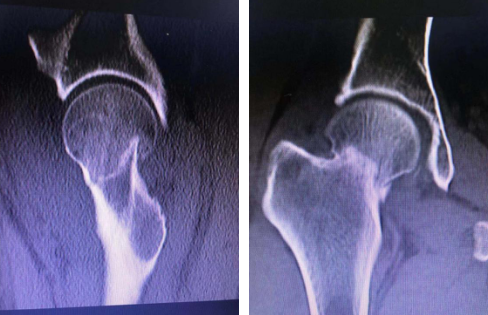

患者葛大姐,47岁,上班时滑倒,右髋部着地,疼痛难忍,不能活动,在当地医院摄片显示右股骨颈骨折,随后被送到betway在线登陆治疗。

创伤骨科张子阳医生接诊,检查发现,患者右股骨颈骨折,断端错位,需要进行手术复位,但传统的切开复位钢板内固定,患者创伤大,术后并发症多,手术费用高。手术小组经过讨论,决定采用机器人辅助下闭合复位空心螺钉内固定术,手术创伤小,术中出血少,更利于患者术后恢复。

术中,先将患者置于牵引床上闭合复位,C型臂透视见骨折端对位良好;接着,机器人C型臂透视对患者股骨颈部位进行三维扫描,图像被同步传输至骨科手术机器人系统。同时,在导航系统屏幕上规划好钉道。随后,机器人的机械臂将手术工具精确定位到手术位置,套筒指向目的钉道的进钉点。手术小组沿着套筒钻入导引针,确认位置无误,再把空心加压螺钉通过导引针固定,拔出导针。

手术历时40分钟,顺利完成。创伤骨科任海东主任说,以往股骨颈骨折如何精准置钉一直是个难题,但在机器人导航辅助下,手术团队将精确度误差控制在0.2毫米以内。整个手术过程中,透视次数大幅减少,对患者及医护人员的放射保护大大增强。创口仅1厘米,患者术后几乎感觉不到疼痛。